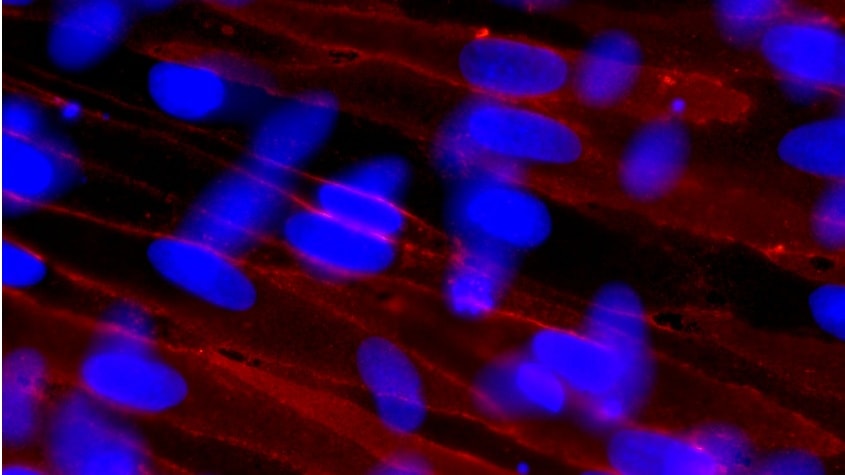

These hepatic non-parenchymal cells provide scientists with the building blocks to create more physiologically relevant in vitro models, including co-cultures and 3D cell cultures, for enhanced liver disease research.

Hepatic non-parenchymal cells are involved in normal liver function, including transport, metabolism and growth; however, they also play important roles in the immune response. Kupffer cells, for instance, are the resident macrophages of the liver and are one of the first lines of defense against bacteria and toxins in the gut. In addition, liver-derived endothelial cells form the primary cellular barrier that lines blood vessels and sinusoids in the liver.

As well as their role in normal liver function, hepatic non-parenchymal cells can be involved in the formation of common liver diseases. For example, when the liver is damaged, stellate cells can differentiate to form myofibroblasts, leading to collagen deposition, which can result in cirrhosis. Therefore, by creating more sophisticated in vitro culture models that incorporate both hepatocytes and non-parenchymal cells, scientists can improve the translatability of their toxicity testing and pharmacokinetics studies to clinical trials, thus aiding the development of new liver disease treatments.